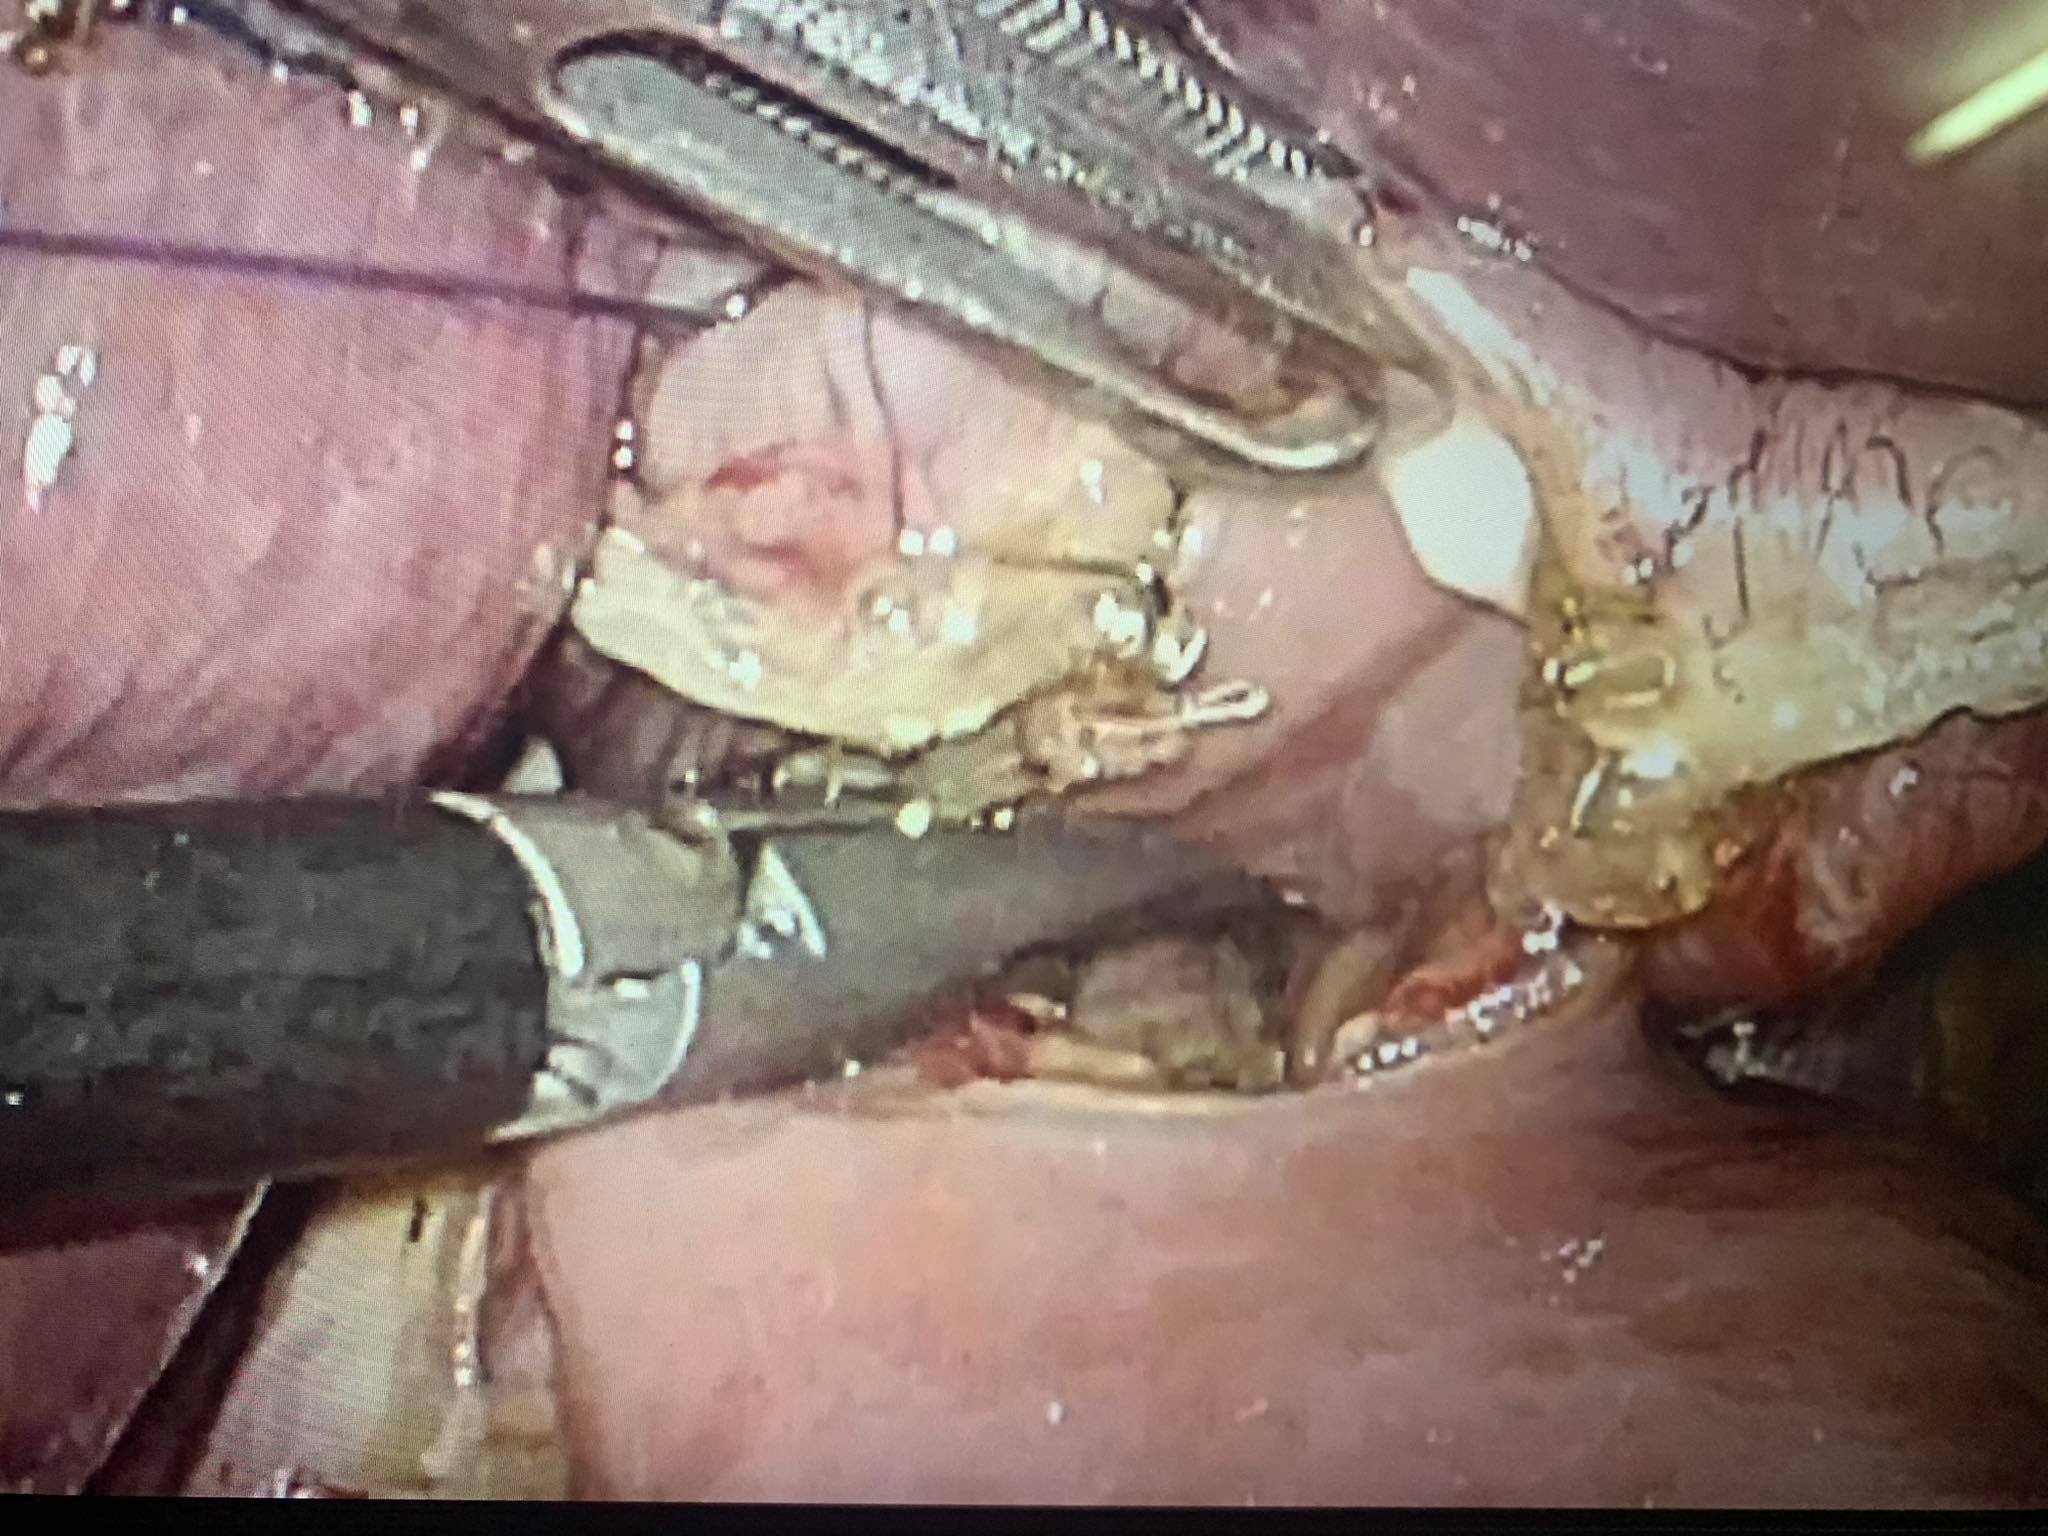

Hình 3: Miệng nối thực quản-hỗng tràng thực hiện bằng stapler thẳng.